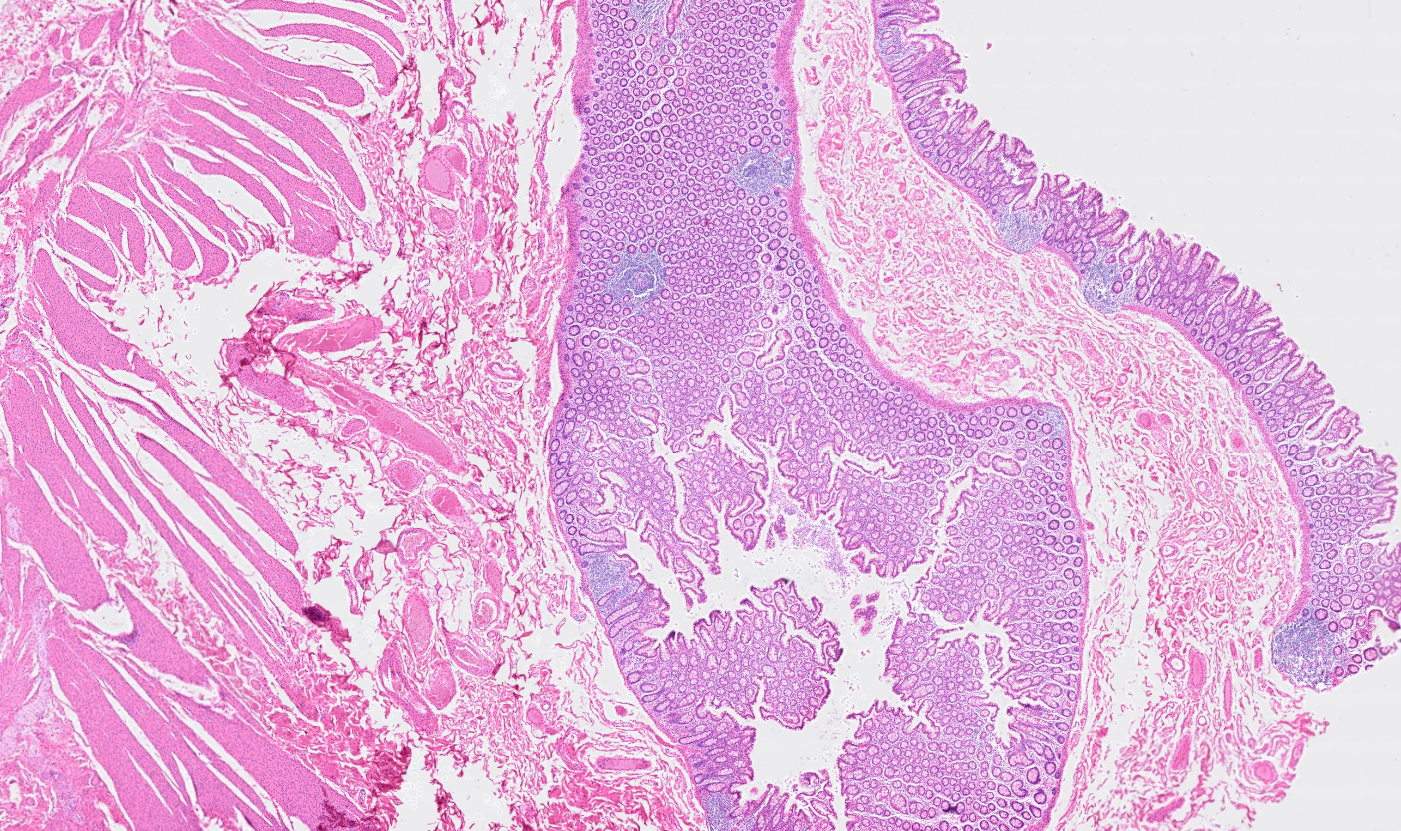

Applicability across many tissue types

The segmentation module is designed to generalize across a wide range of biological tissues. Below are representative benchmark results based on 10x Genomics demo datasets:

Colon

Applicability across different spatial resolutions

The segmentation module is designed to help researchers explore tissue architecture at multiple levels of detail, depending on their scientific question. Users can begin by dividing the tissue into major anatomical structures to gain a broad overview of the spatial landscape. From there, they can zoom into a specific region of interest and further segment it into sub-tissue compartments, enabling more refined analysis of microenvironments and localized biological processes.